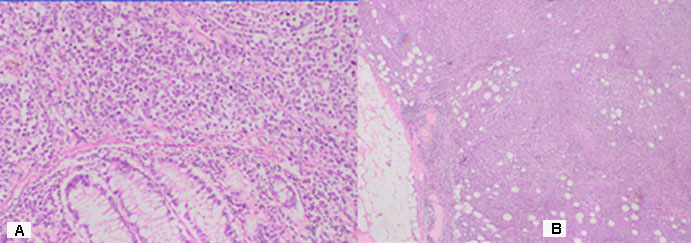

The result of a histological findings - Macroscopic

Part of a thick intestine with a size of 30 cm with a omentum. In the middle part of the resectеd colon, there is a tumor formation with a diameter of 10 cm. Eccentrically encompassing the intestine along the 10 cm. The tumor has a whitish color and macroscopically resembles fish meat. Seven lymph nodes were removed. Microscopic -Part of a thick intestine with a tumor histologically represented by diffuse cultivated tumor cells with scarce cytoplasm, circular polymorphic nuclei with visible nucleoli and high mitotic activity / over 10 mitoses per 10 high-power fields. The wall of colon with massive, diffuseinfiltration from large and medium-sized neoplastic cells. They have a slightly pronounced polymorphism, a dischositive way of growth, some of them with vesicular nuclei and prominent nucleoli (Figure 3A,C). Well taken out Reed-Sternberg like cells (Figure 3B). There are extensive zones with epithelium atrophy. The tumor infiltrates mucose, submucosa, smooth muscle layer, subset fat and serosis (Figure 4A). Morphology is a characteristic of MALT lymphoma. In three of the surveyed seven lymph nodes, a diffuse deletion structure was established due to tumor infiltration (Figure 4B). The resection lines are clean, without tumor infiltration. To establish the type of lymphoma, Immunohistochemical (IHC) analysis is imposed.

Figure 3: Microscopic histological findings: (A) The tumor histologically represented by diffuse cultivated tumor cells with scarce cytoplasm, circular polymorphic nuclei with visible nucleoli and high mitotic activity / over 10 mitoses per 10 high-power fields H&E, x20. (B) Well taken out Reed-Sternberg like cells (mentioned with black arrow) H&E, x20. (C) The wall of colon with massive, diffuse infiltration from large and medium-sized neoplastic cells. They have a slightly pronounced polymorphism, a dischositive way of growth, some of them with vesicular nuclei and prominent nucleoli H&E, x200.

Figure 4: (A) The wall of colon with massive, diffuse infiltration from large and medium-sized neoplastic cells with slightly pronounced polymorphism, a dischositive way of growth, some of them with vesicular nuclei and prominent nucleoli H&E, x100. (B) In three of the surveyed seven lymph nodes, a diffuse deletion structure was established due to tumor infiltration H&E, x20.

DLBCL is neoplasm of large B lymphoid cells with nuclei at least 2× size of lymphocyte [20]. The pathomorphological characteristic is expressed by diffuse growth pattern with large cells (usually 5× normal lymphocytes) resembling immunoblasts (amphophilic cytoplasm, eccentric nuclei with one central nucleoli) or centroblasts (pale or basophilic cytoplasm, vesicular chromatin due to chromatin margination, 2 - 3 nucleoli, often near membrane), or rarely, anaplastic, associated with neutrophils [21]. In Figure 3 we present diffuse tumor cells with scarce cytoplasm, circular polymorphic nuclei with visible nucleoli and high mitotic activity / over 10 mitoses per 10 high-power fields. In Figure 4A is clearly seen the wall of colon with massive, diffuse infiltration from large and medium-sized neoplastic cells with slightly pronounced polymorphism, a dischositive way of growth, some of them with vesicular nuclei and prominent nucleoli. In three of the surveyed seven lymph nodes, a diffuse deletion structure was established due to tumor infiltration (Figure 4B).